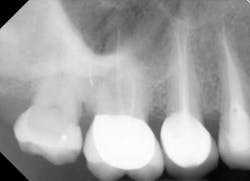

1. Not all teeth should be treated the same. Anatomy dictates technique. Having only one clinical instrumentation or obturation technique is not adequate when the tooth dictates a different method than the one generally employed. For example, if the clinician only has standard K files (Mani K files) and the canal is calcified, having the option of employing a hand K file designed for such calcification (Mani D finders) allows more efficient negotiation of calcification. Having only one hand file option or using the wrong hand file can lead to iatrogenic outcomes (blocked, ledged canals among other issues). See Figs. 1-2. Similarly, using a crown-down approach to instrumentation may risk iatrogenic outcomes when a step-back approach is more appropriate.